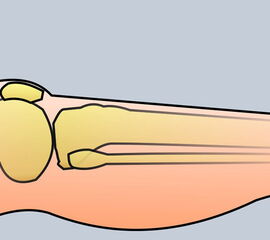

Technik:

Die Zehe wird unter Bildung eines größeren plantaren Lappens fischmaul-artig umschnitten. Anschließend wird der Knochen soweit gekürzt, dass ein spannungsfreier Hautverschluss möglich ist.